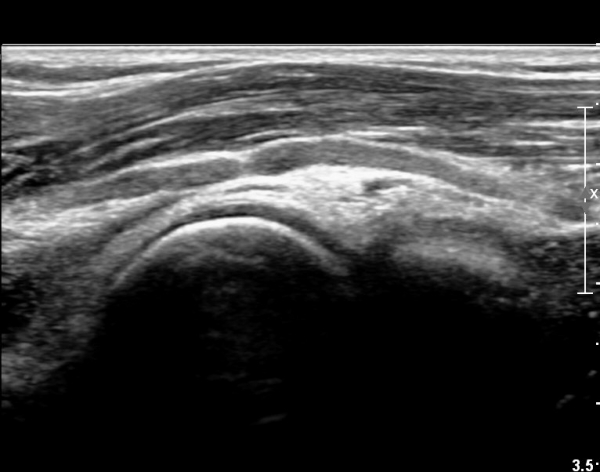

ÆÈ²ÞÄ¡ ¾Õ Èİñ°£½Å°æ Á¾´Ü¸é°Ë»ç¿¡¼ Èİñ±ä»ê°æÀÌ ºÎ¾îÀÖ°í ±¹¼ÒÀûÇùÂøÀÌ °üÂûµÈ´Ù(»çÁø 4)..